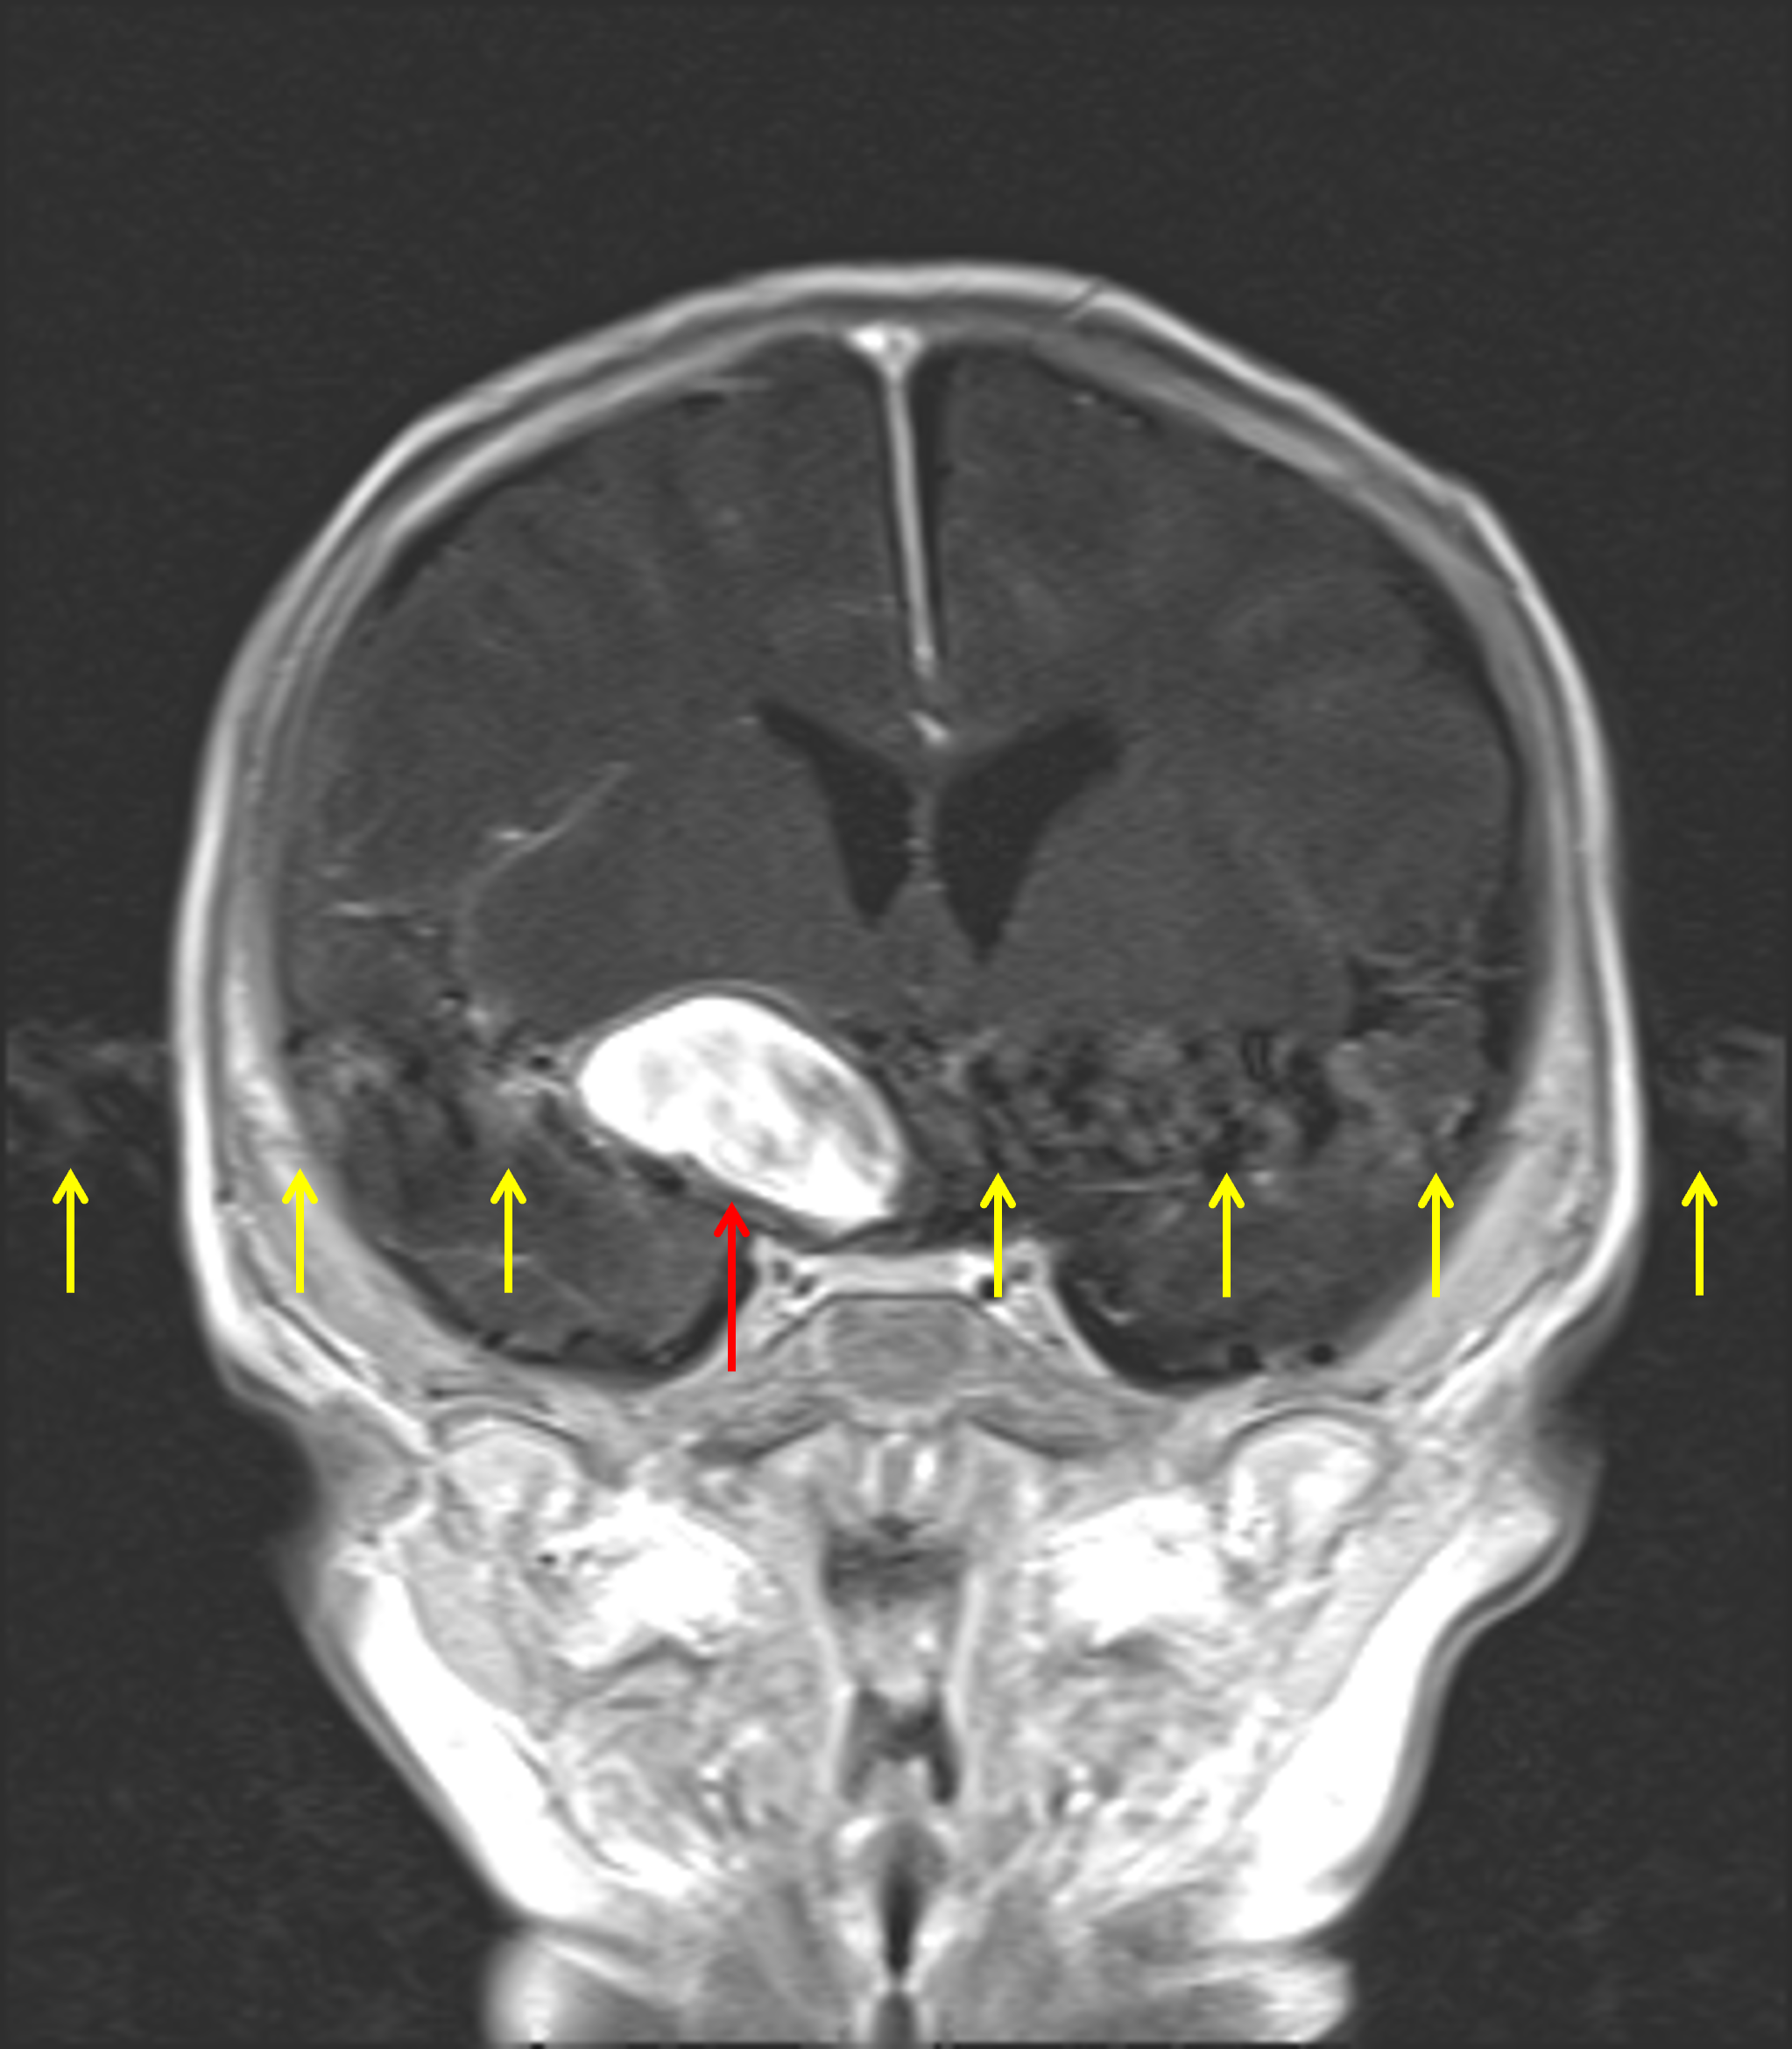

Age: 2 months

Sex: Female

Indication: Fussiness, bulging anterior fontanelle

MRI

Giant cerebral aneurysm